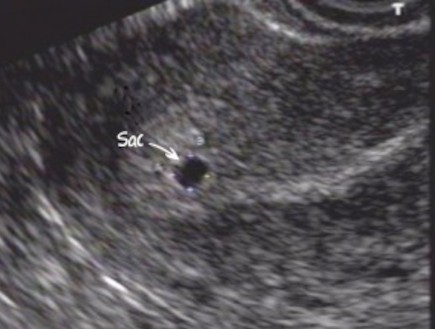

היו ימים שהיא תהתה אם הוא עוד חי, והיו כאלו שהיא שאלה את עצמה אם הוא אי פעם אהב אותה. המקום שלה בעולם התערער. היא לא ידעה אל מי לפנות. היא ידעה שהוא לא מת, היא הבינה שהוא נעלם. לאן? למה? איך הוא עשה את זה? השאלות הללו נותרו עבורה פתוחות, משאירות בתוכה חלל שכל כולו סימן שאלה. כשאורן נעלם, היא איבדה את המקום היציב שלה, את הבסיס שלה. היא לא ידעה אם להתפטר מהעבודה, היא לא ידעה אם לעבור דירה, לעזוב את הארץ, או להתאבד. היא פשוט לא ידעה. ובתוכה, כמו סימן השאלה, אט אט גדלים להם חיים. כגודל השאלה, גודל הנקודה הנראית באולטרסאונד, שהולכת וגדלה, ומביאה איתה שאלה בפני עצמה.

וככה נמשכו להם החודשים, והחלומות העצובים הלכו ופחתו, יותר ויותר הצחוק השתלט עליהם. ולפעמים כבר לא חלמה בכלל. הקיץ נגמר, הנקודה טפחה וגדלה, לבשה צורת חיים, פיתחה גפיים, ידיים ורגליים. הבטן טפחה. היריון.